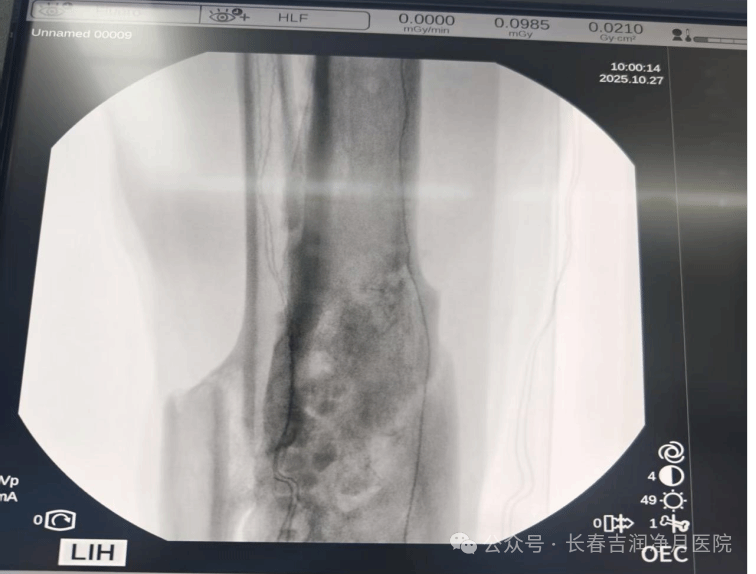

2025年10月,张先生入住我院接受决定性治疗。于铁成主任团队经过充分准备,为患者实施第二阶段手术。术中通过精准操作,完整取出抗生素链珠,彻底清创后植入抗生素硫酸钙骨粉。手术过程顺利,耗时短,创伤小。

(2025年10月,第二次手术术中胫腓骨正侧位)